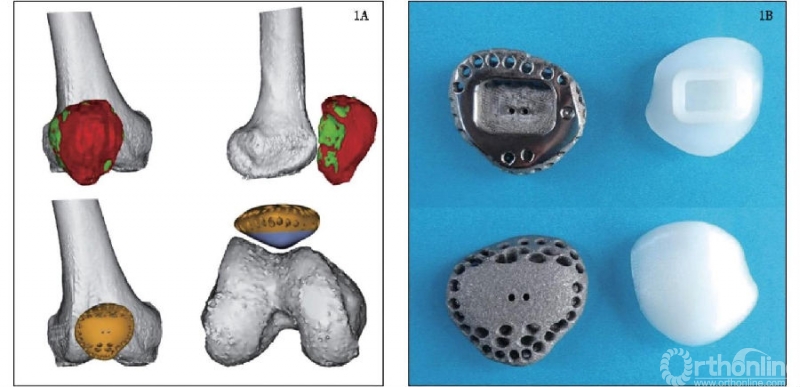

北京大学人民医院团队[3]应用3D打印金属假体重建四肢骨肿瘤切除术后大段骨关节缺损,弥补了传统生产工艺及手术技术的缺陷,为四肢大段骨缺损的重建提供了新思路,其团队应用3D打印定制肱骨远端半肘关节假体重建肘关节恶性肿瘤切除术后骨缺损。MSTS93评分为19~28分,平均24.1分;获优8例,良2例。VAS评分为(0.9±1.0)分,较术前(5.9±1.0)分明显改善,差异有统计学意义。